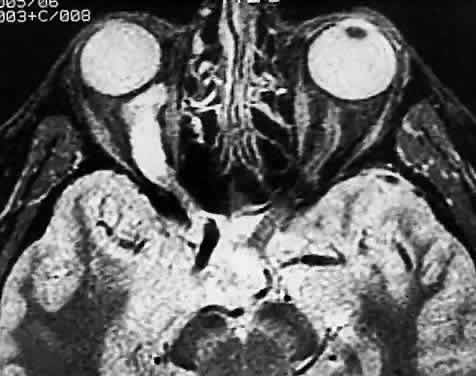

Computed tomographic (CT) and magnetic resonance imaging (MRI) have had a significant impact on the management of patients.29 Many tumors are diagnosed based on imaging features alone, without tissue confirmation (Fig. 35). They typically show a demarcated fusiform enlargement of the nerve, which may be kinked and indent the globe. On T2-weighted MRI, a circumferential component surrounds a compact core of low signal intensity.23 MRI is particularly useful in assessing the extent of the lesion.

Fig. 35. Computed tomographic scan showing left optic nerve glioma.

Fig. 40. Bilateral optic nerve gliomas in a patient with neurofibromatosis. Computed tomography.